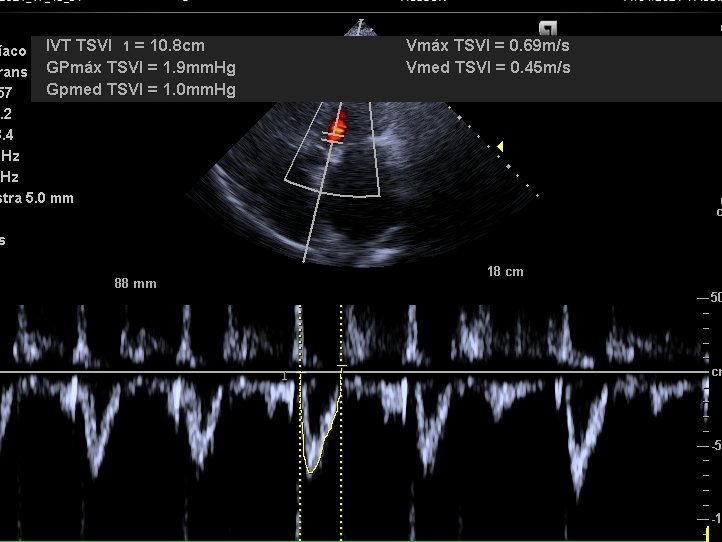

Severe TR in rheumatic🫀 disease with mitral stenosis. Very dilated LA and RA (chronic elevation of pressures), and a small collapsible IVC. Normal Portal Vein (not needed). Average LVOT VTI (atrial fibrillation) = 12

Clear cut case of overdiuresis causing low stroke volume! 2/3